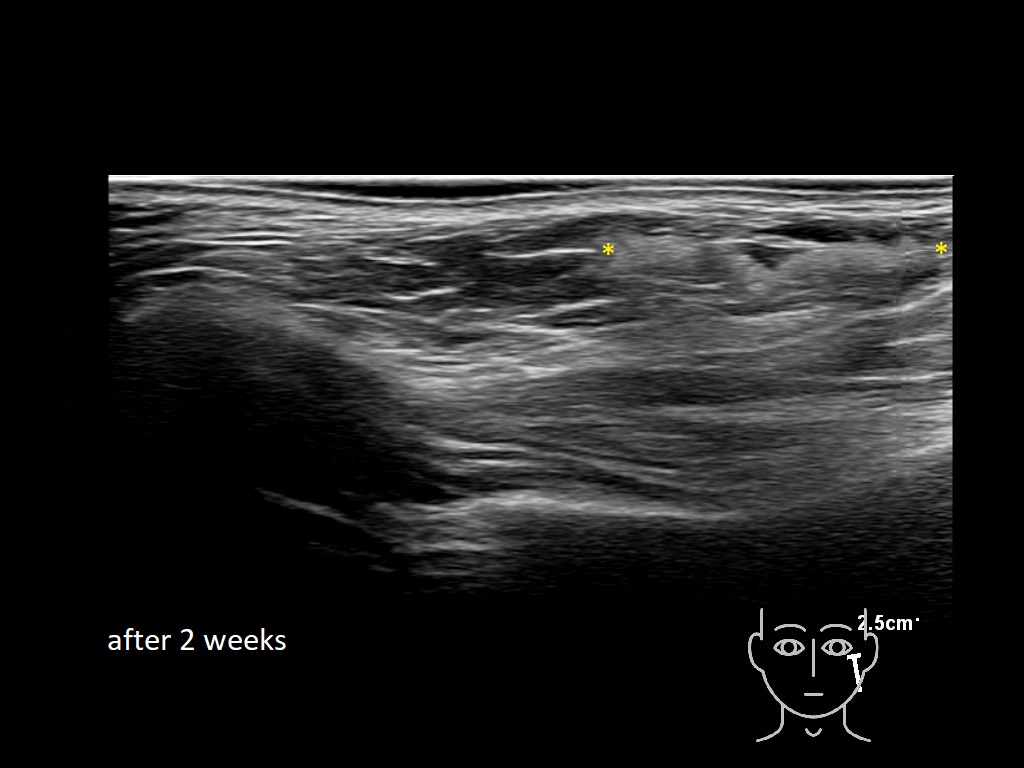

Draw in the image on the right where the fillers are located. To check if your answer is correct, please click on the secondary image.

Fillers

Draw in the second image below where the fillers are located. To check if your answer is correct, swipe the first image to the right.